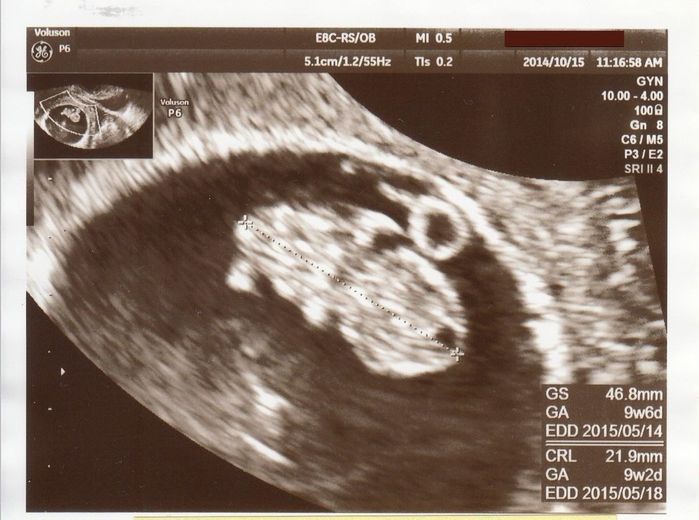

おなかの中ですくすく成長する赤ちゃん - 妊娠9週目のエコー写真

右側が頭、左側が体です。頭と体がなんとなく分かれて、体の下側に小さな手と足がついています。「頑張って成長してくれているな」とうれしくなりました。2番目の子を連れて産院に行ったのですが、診察室には入らず、前室で看護師さんとおもちゃで遊びながら大人しく待っていてくれました。